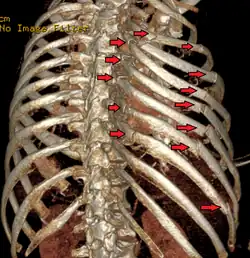

![]() Radiografía de tórax en la que son visibles varias fracturas costales señaladas por un óvalo en el hemitórax izquierdo. | ||

El diagnóstico se basa en la sintomatología y la exploración del paciente que detecta una serie de signos específicos. Las pruebas complementarias más utilizadas para confirmar el diagnóstico son la radiografía de tórax y la tomografía axial computarizada en caso de traumatismos graves.[2]